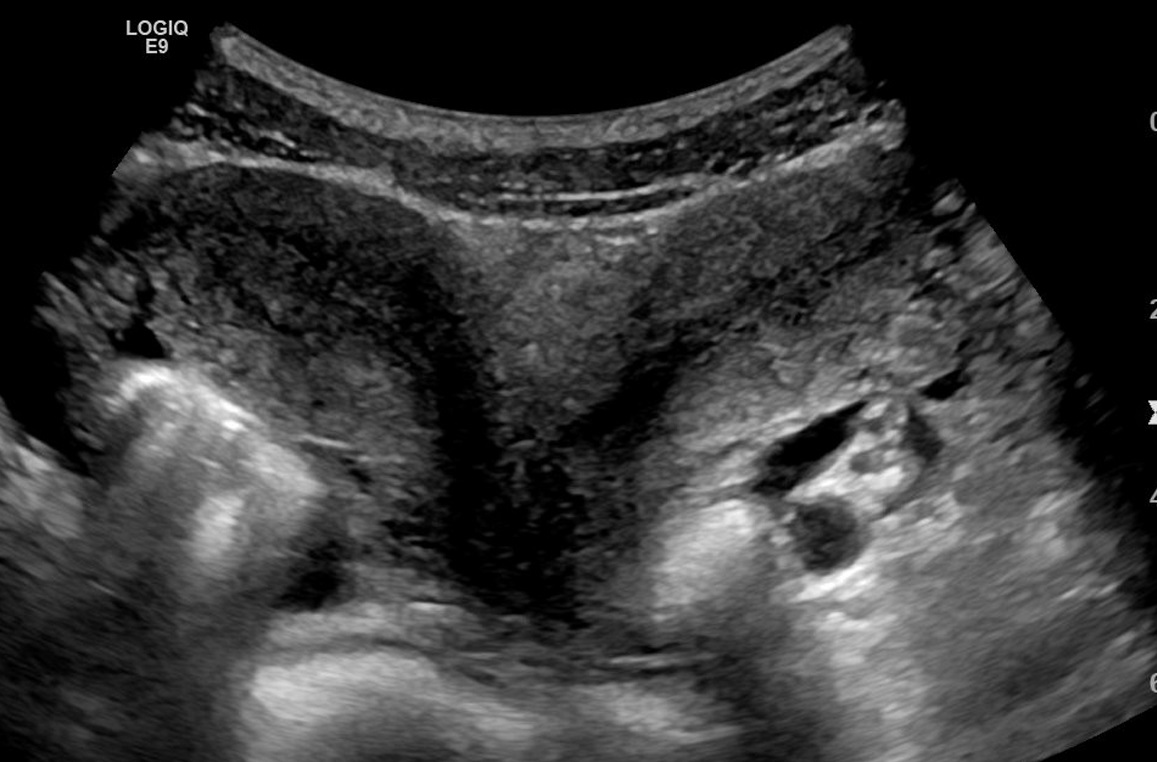

Ultrassonografia de um útero didelfo (Reprodução/Wikimedia Commons/Mme Mim)

No caso da mãe de Bangladesh, a condição certamente não havia sido descoberta até a sua ida à emergência do hospital, quando os médicos a submeteram a uma ultrassonografia e descobriram o segundo útero e os gêmeos dentro dele. Os bebês tiveram que nascer por meio de uma cesariana — os obstetras que realizaram a cirurgia contaram que jamais tinham se deparado com algo parecido.